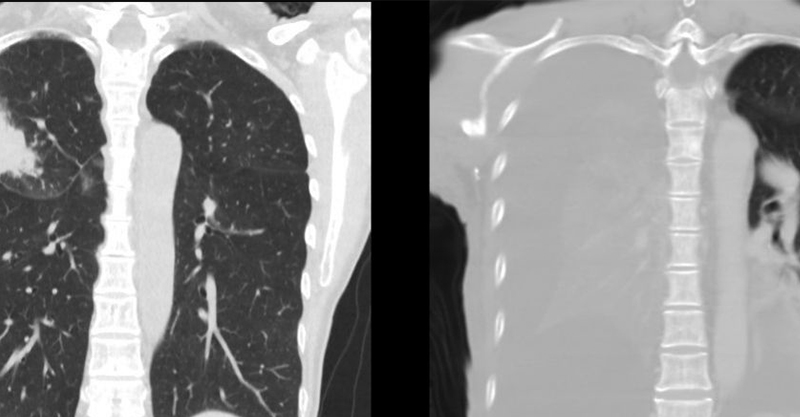

阿嬤餵孫吃整顆花生 1歲孫「肺部開始塌陷」醫氣炸:到底還要講幾次?嬰幼兒的身體尚未發育完全,所以飲食方面要格外注意。小兒科醫師廖穗綾就在臉書粉專分... February 13, 2026 健康, 台灣, 知識